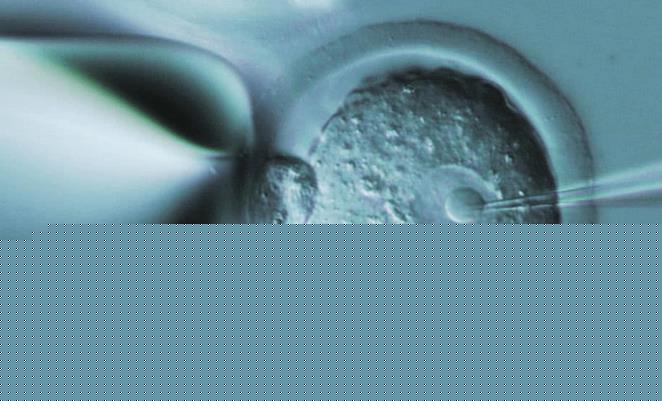

试管婴儿流程大致分为进周促排、取卵取精、胚胎培养、检测与移植,涉及到不同的阶段其费用会存在差异,本身做试管婴儿的费用、流程、成功率无外乎是姐妹们最为关心的几个问题,以下就给大家分享关于该医院的试管费用。